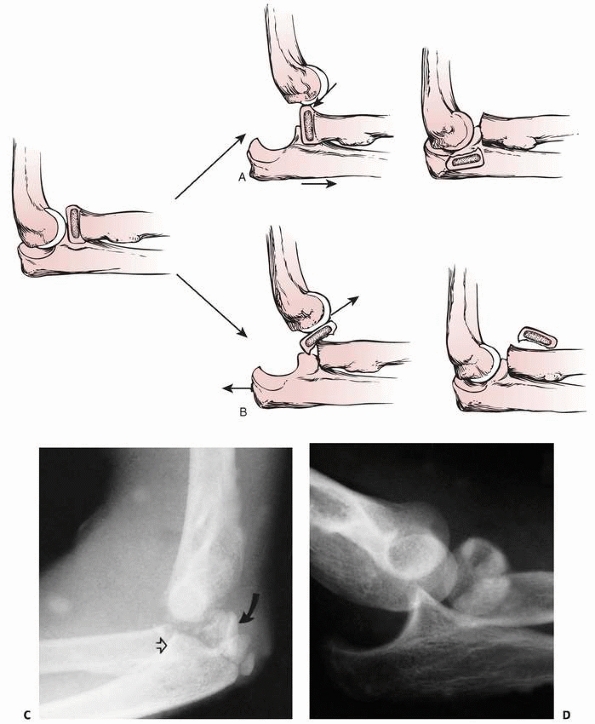

FIGURE 11-8 Dislocation fracture patterns. A.

Type D: The radial neck is fractured during the process of reduction by the capitellum pressing against the distal lip of the radial head.125 B. Type E: The radial neck is fractured during the process of dislocation by the capitellum pressing against the proximal lip of the radial head.98 C. Radiographs of a radial head that was fractured during the reduction of the dislocation (type D). The radial head (solid arrow) lies posterior to the distal humerus, and the distal portion of the neck (open arrow) is anterior. (Courtesy of Richard E. King, MD.) D. Radiograph of the dislocated elbow in which the fracture of the radial neck occurred during the process of dislocation (type E). |